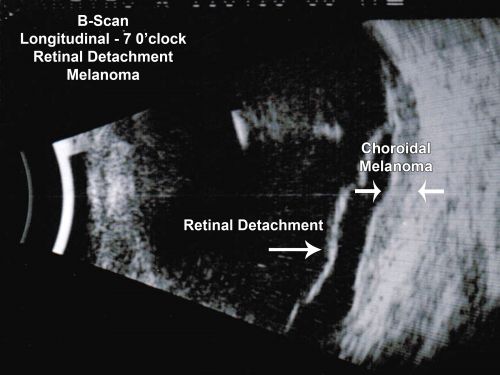

Choroidal Melanoma - Exudative Retinal Detachment 82 Year Old Man B Scan Ultrasound Longitudinal

82-year-old man who had 3 falls 2 weeks ago. After the falls he started checking his vision and noticed there was a veil over the left eye, which he had seen for about two weeks in the superior visual field.  OD 20/25,  OS 20/40

(patient was medically never well enough for brachytherapy and died 6 months later from heart disease)